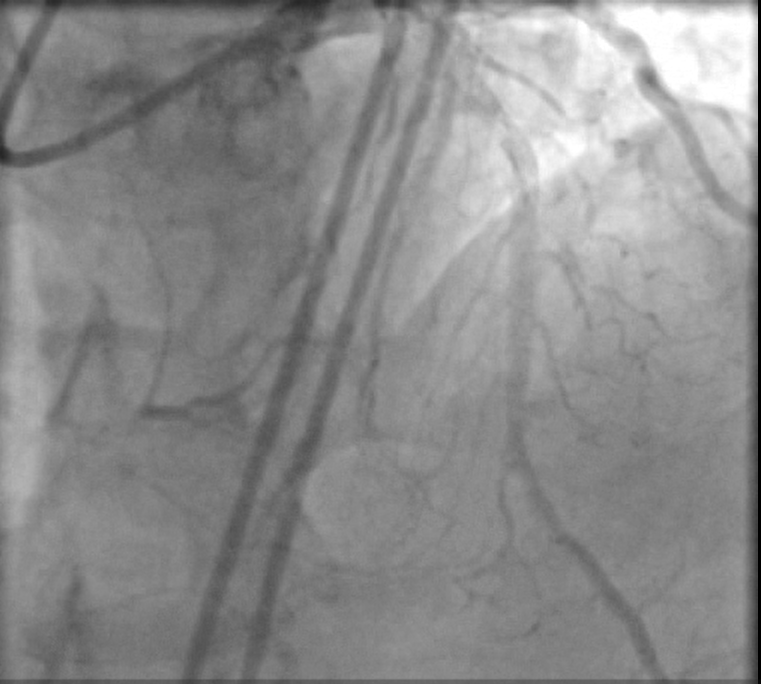

LM : Normal vessel bifurcating into LAD & LCX.LAD : Atherosclerotic vessel with patent previously deployed stent .LCX: A atherosclerotic small diffusely diseased vessel .RCA : Atherosclerotic vessel with proximal CTO with bridging collaterals and retrograde good septal and epicardial collaterals from left system

Dual femoral access , Dual injection through AL1 7F & XB4 7F Target vessel assessment ( RCA ) with calculation of J-CTO score then deciding which strategy we decided a Trial antegrade, If failed , Retrograde through septals , If failed , shift to epicardial collateral.Antegrade Trial with GAIA Wires , Corsair MC failed , Retrograde trial through septals failed as it seems not connected shifting strategy to epicardial : Sion blue navigated through epicardial collaterals , corsair 150 MC successfully passed through PL branch MC advanced to distal Cap & GAIA 2nd wire successfully pierced distal cap , but failed to entre antegrade guide Trial snaring through AL guiding by a home made snare but failed , Guiding changed to JR with successful snaring of wire into antegrade guide followed by MCPilot 50 wire introduced through retrograde MC ( Rendezvous Technique , Reverse TIP IN ) then MC Withdrawn we started conventional PCI with Antegrade Balloon dilatation 2.5 * 15 mm semicompliant then 3.5 * 15 mm NC balloons Then stenting with 2 overlapping DES with postdialtation with 4*15 NC balloon with final good angiographic results